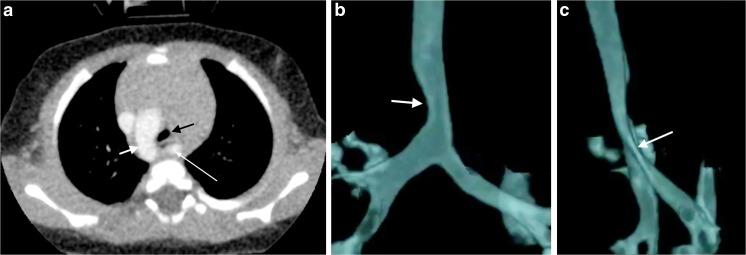

This retrospective review of 33 children's dynamic 4-dimensional (4-D) computed tomography (CT) images of the airways, performed using volume scanning on a 320-detector array without anaesthesia (free-breathing) and 1.4-s continuous scanning, was undertaken to report technique, pitfalls, quality, radiation doses and findings. Tracheobronchomalacia (airway diameter collapse >28%) was recorded. Age-matched routine chest CT scans and bronchograms acted as benchmarks for comparing effective dose. Pitfalls included failure to administer intravenous contrast, pull back endotracheal tubes and/or remove nasogastric tubes. Twenty-two studies (67%) were diagnostic. Motion artefact was present in 16 (48%). Mean effective dose: dynamic 4-D CT 1.0 mSv; routine CT chest, 1.0 mSv, and bronchograms, 1.4 mSv. Dynamic 4-D CT showed tracheobronchomalacia in 20 patients (61%) and cardiovascular abnormalities in 12 (36%). Fourteen children (70%) with tracheobronchomalacia were managed successfully by optimising conservative management, 5 (25%) underwent surgical interventions and 1 (5%) died from the presenting disorder.

本研究回顾性分析了33例儿童气道动态四维(4-D)计算机断层扫描(CT)图像,使用320排探测器阵列进行容积扫描,无需麻醉(自由呼吸)且连续扫描1.4秒,旨在报告技术、陷阱、质量、辐射剂量及结果。记录气管支气管软化(气道直径塌陷>28%)情况。年龄匹配的常规胸部CT扫描和支气管造影作为比较有效剂量的基准。陷阱包括未给予静脉造影剂、拔出气管内导管和/或移除鼻胃管。22项研究(67%)具有诊断价值。16项研究(48%)存在运动伪影。平均有效剂量:动态4-D CT为1.0 mSv;常规胸部CT为1.0 mSv,支气管造影为1.4 mSv。动态4-D CT显示20例患者(61%)存在气管支气管软化,12例患者(36%)存在心血管异常。14例(70%)气管支气管软化患儿通过优化保守治疗成功治愈,5例(25%)接受了手术干预,1例(5%)因原发病死亡。